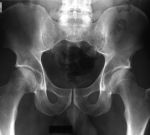

Отмечается диффузный остеопороз. Высота межпозвонковых пространств неравномерно снижена, замыкательные пластинки склерозированы, деформированы, имеются грубые краевые остеофиты, на уровне Th9-L1 передняя продольная связка обызвествлена. На уровне L1-S1 выражен межостистый артроз. Суставные поверхности дугоотростчатых суставов склерозированы, деформированы, суставные щели резко сужены. Диск L4-L5 пролабирует циркулярно до 4,5мм. Диск L5-S1 с вакуум- эффектом. Крестцово-подвздошные сочленения не изменены. Копчик обычной формы, размеров, положения.

ЗАКЛЮЧЕНИЕ: Единичные кисты печени. Киста левой почки. Неполное удвоение правой почки. Диффузный остеопороз. Выраженный остеохондроз, деф. спондилез, спондилоартроз нижнегрудного и пояснично-креспщового отделов позвоночника. Фиксирующий лигаментоз в сегментах Тh9-L1. Протрузия диска L4-L5.